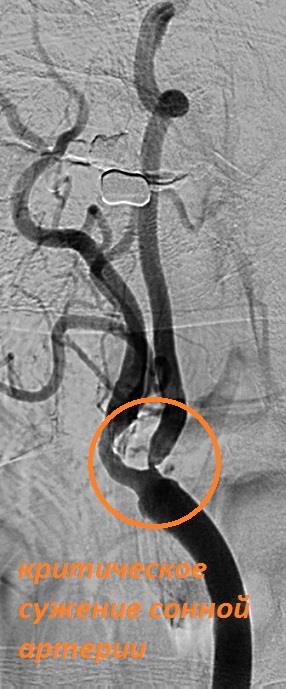

Бифуркация оса асб

Бифуркация оса асб 115 фотографий